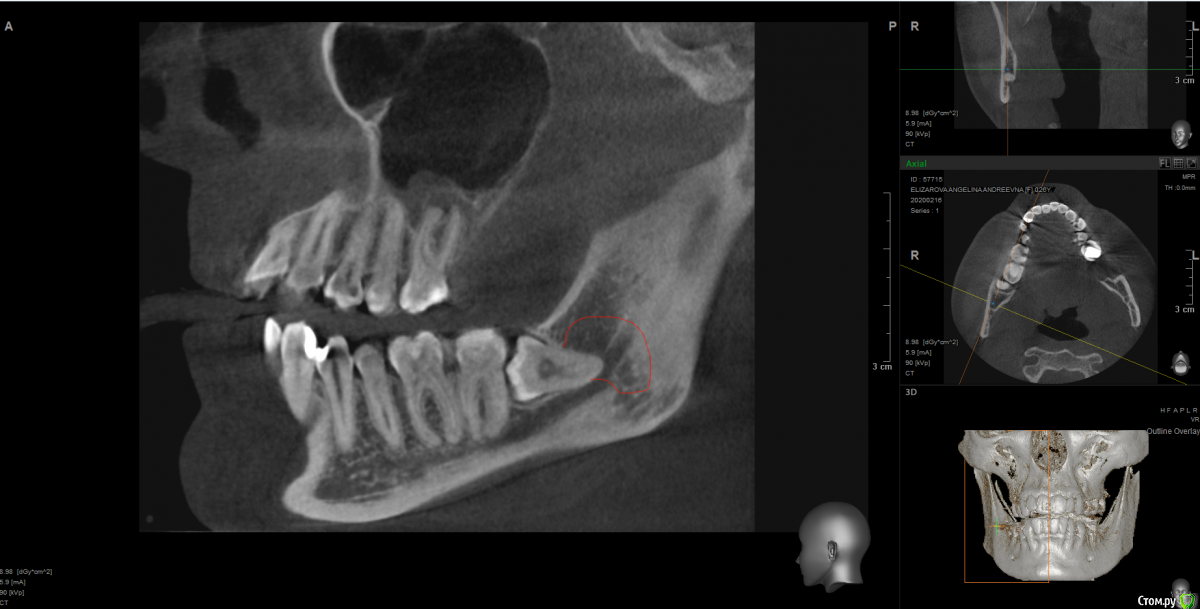

It'sGeorgy Опубликовано 17 февраля, 2020 Поделиться Опубликовано 17 февраля, 2020 Доброго времени суток! Пациентка жалуется на чувство онемения справа в области нижней челюсти. На КТ вот такая картина:Не вижу больших проблем с удалением зуба, но не могу понять есть ли новообразование в челюсти, и, если есть, каковы его размеры:или? Заранее спасибо за помощь. Ссылка на комментарий

Dr.Berger Опубликовано 18 февраля, 2020 Поделиться Опубликовано 18 февраля, 2020 Доброго времени суток! Пациентка жалуется на чувство онемения справа в области нижней челюсти. На КТ вот такая картина:Screenshot_4.pngНе вижу больших проблем с удалением зуба, но не могу понять есть ли новообразование в челюсти, и, если есть, каковы его размеры:восемь1.pngиливосемь2.png? Заранее спасибо за помощь.а что на КТ у 47 зуба? Там периодонтит!? Ссылка на комментарий

Дмитрий М Опубликовано 23 февраля, 2020 Поделиться Опубликовано 23 февраля, 2020 чувство онемения справа в области нижней челюсти возможно даже и 48 не причина! +1 кисты не вижупочему сразу решили что причина в 8-ом зубе? ментальное смотрите, проверьте все зубы, верхнюю 8-ку, определите область онемения на коже, может у пациента больше жалоб чем клиники Ссылка на комментарий